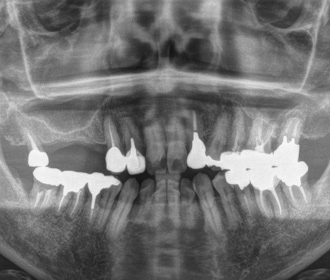

矯正治療、骨移植を伴うインプラント治療、セラミック・クラウン等による機能的、審美的治療

矯正治療、骨移植を伴うインプラント治療、セラミック・クラウン等による機能的、審美的治療

術前